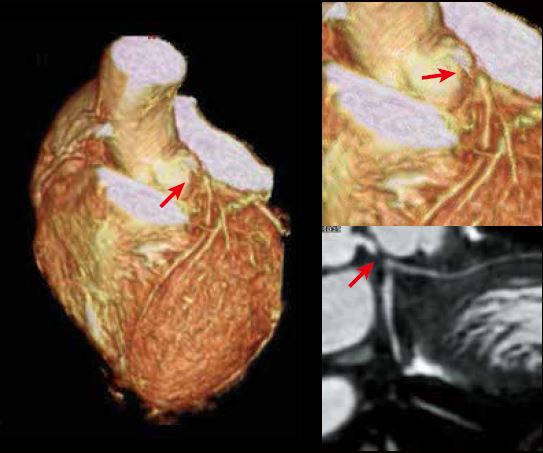

Клінічний випадок 1

Історія пацієнта

Чоловік 75 років, який 2 місяці тому хворів на стенокардію напруги. Його направили до нашого центру візуалізації для оцінки ішемічної хвороби серця.

Successful PCI to LMT Lesion

До

Після

LMT Stenosis on Coronary MRA

LAD

Стрес-перфузія МРТ показала стрес-індуковані дефекти перфузії в передньоперегородці (anteroseptum) та бічній стінці, що свідчить про багатосудинне захворювання коронарної артерії, наприклад ліву передню низхідну і ліву огинаючу артерію. Пізнє посилення гадолінію (ППГ) показало невелику яскраву пляму в субендокарді базальної бічної стінки. Дрібноплямиста ППГ вказувала на нерозпізнаний субендокардіальний інфаркт міокарда. Коронарна МРА виявила зниження сигналу в лівій головній коронарній артерії, що свідчить про високий ступінь стенозу в лівій головній коронарній артерії. Машина швидкої медичної допомоги доставила потерпілого до лікарні для надання невідкладної допомоги. Під час екстреної інвазивної коронарної ангіографії було виявлено стеноз лівої головної коронарної артерії високого ступеня. Подальше черезшкірне коронарне втручання було виконано успішно без жодних ускладнень.